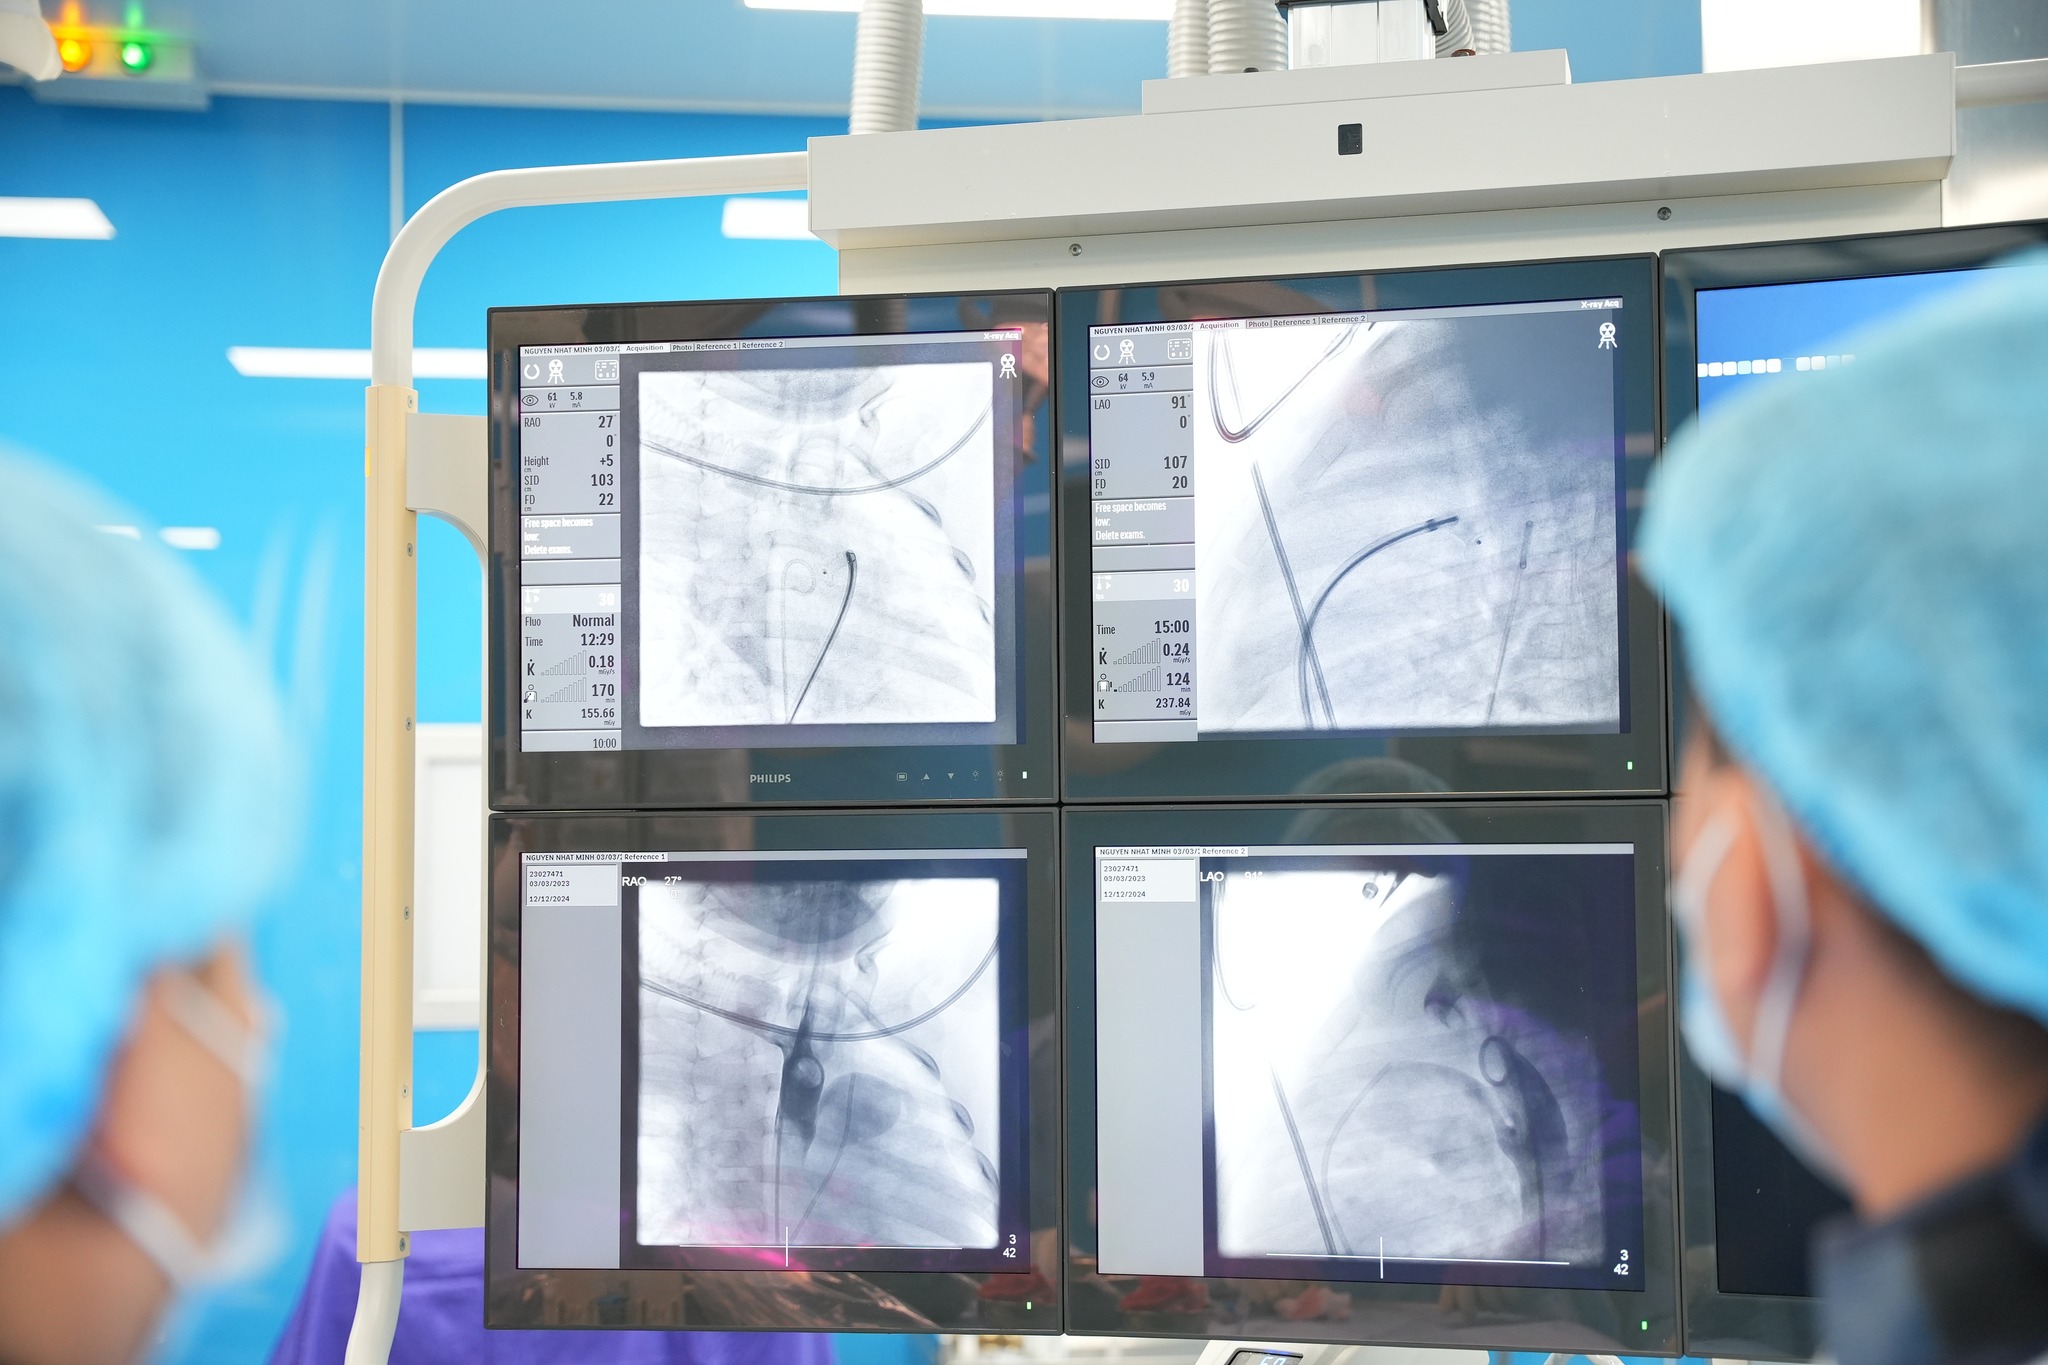

Ngày 11/12/2024, kíp can thiệp tim mạch Bệnh viện Sản Nhi Quảng Ninh tiếp tục triển khai thường quy kỹ thuật can thiệp tim mạch chuyên sâu: thông liên nhĩ, đóng ống động mạch cho 3 bệnh nhi mắc tim bẩm sinh (còn ống động mạch và thông liên nhĩ ) dưới sự hỗ trợ của máy chụp mạch xóa nền hai bình diện (DSA), giúp các trẻ được phục hồi lại trái tim lỗi nhịp ngay tại tỉnh nhà.

Kết quả xét nghiệm và chẩn đoán hình ảnh cho thấy hình ảnh còn ống động mạch, thông liên nhĩ. Qua hội chẩn chuyên khoa, các bác sĩ chẩn đoán và chỉ định can thiệp bít dù ống động mạch cho trẻ.

Với thời gian can thiệp nhanh, không gây tổn thương, bệnh nhân không phải nằm viện lâu như phẫu thuật tim hở. Sau can thiệp, bệnh nhân hồi phục nhanh, có thể ra viện sớm trong vòng từ 2-3 ngày. Sau bít dù thông liên nhĩ ổn định, dù nằm đúng vị trí, các gờ bám tốt, đường về tĩnh mạch chủ trên, tĩnh mạch chủ dưới thoáng, điện tim nhịp xong đều.